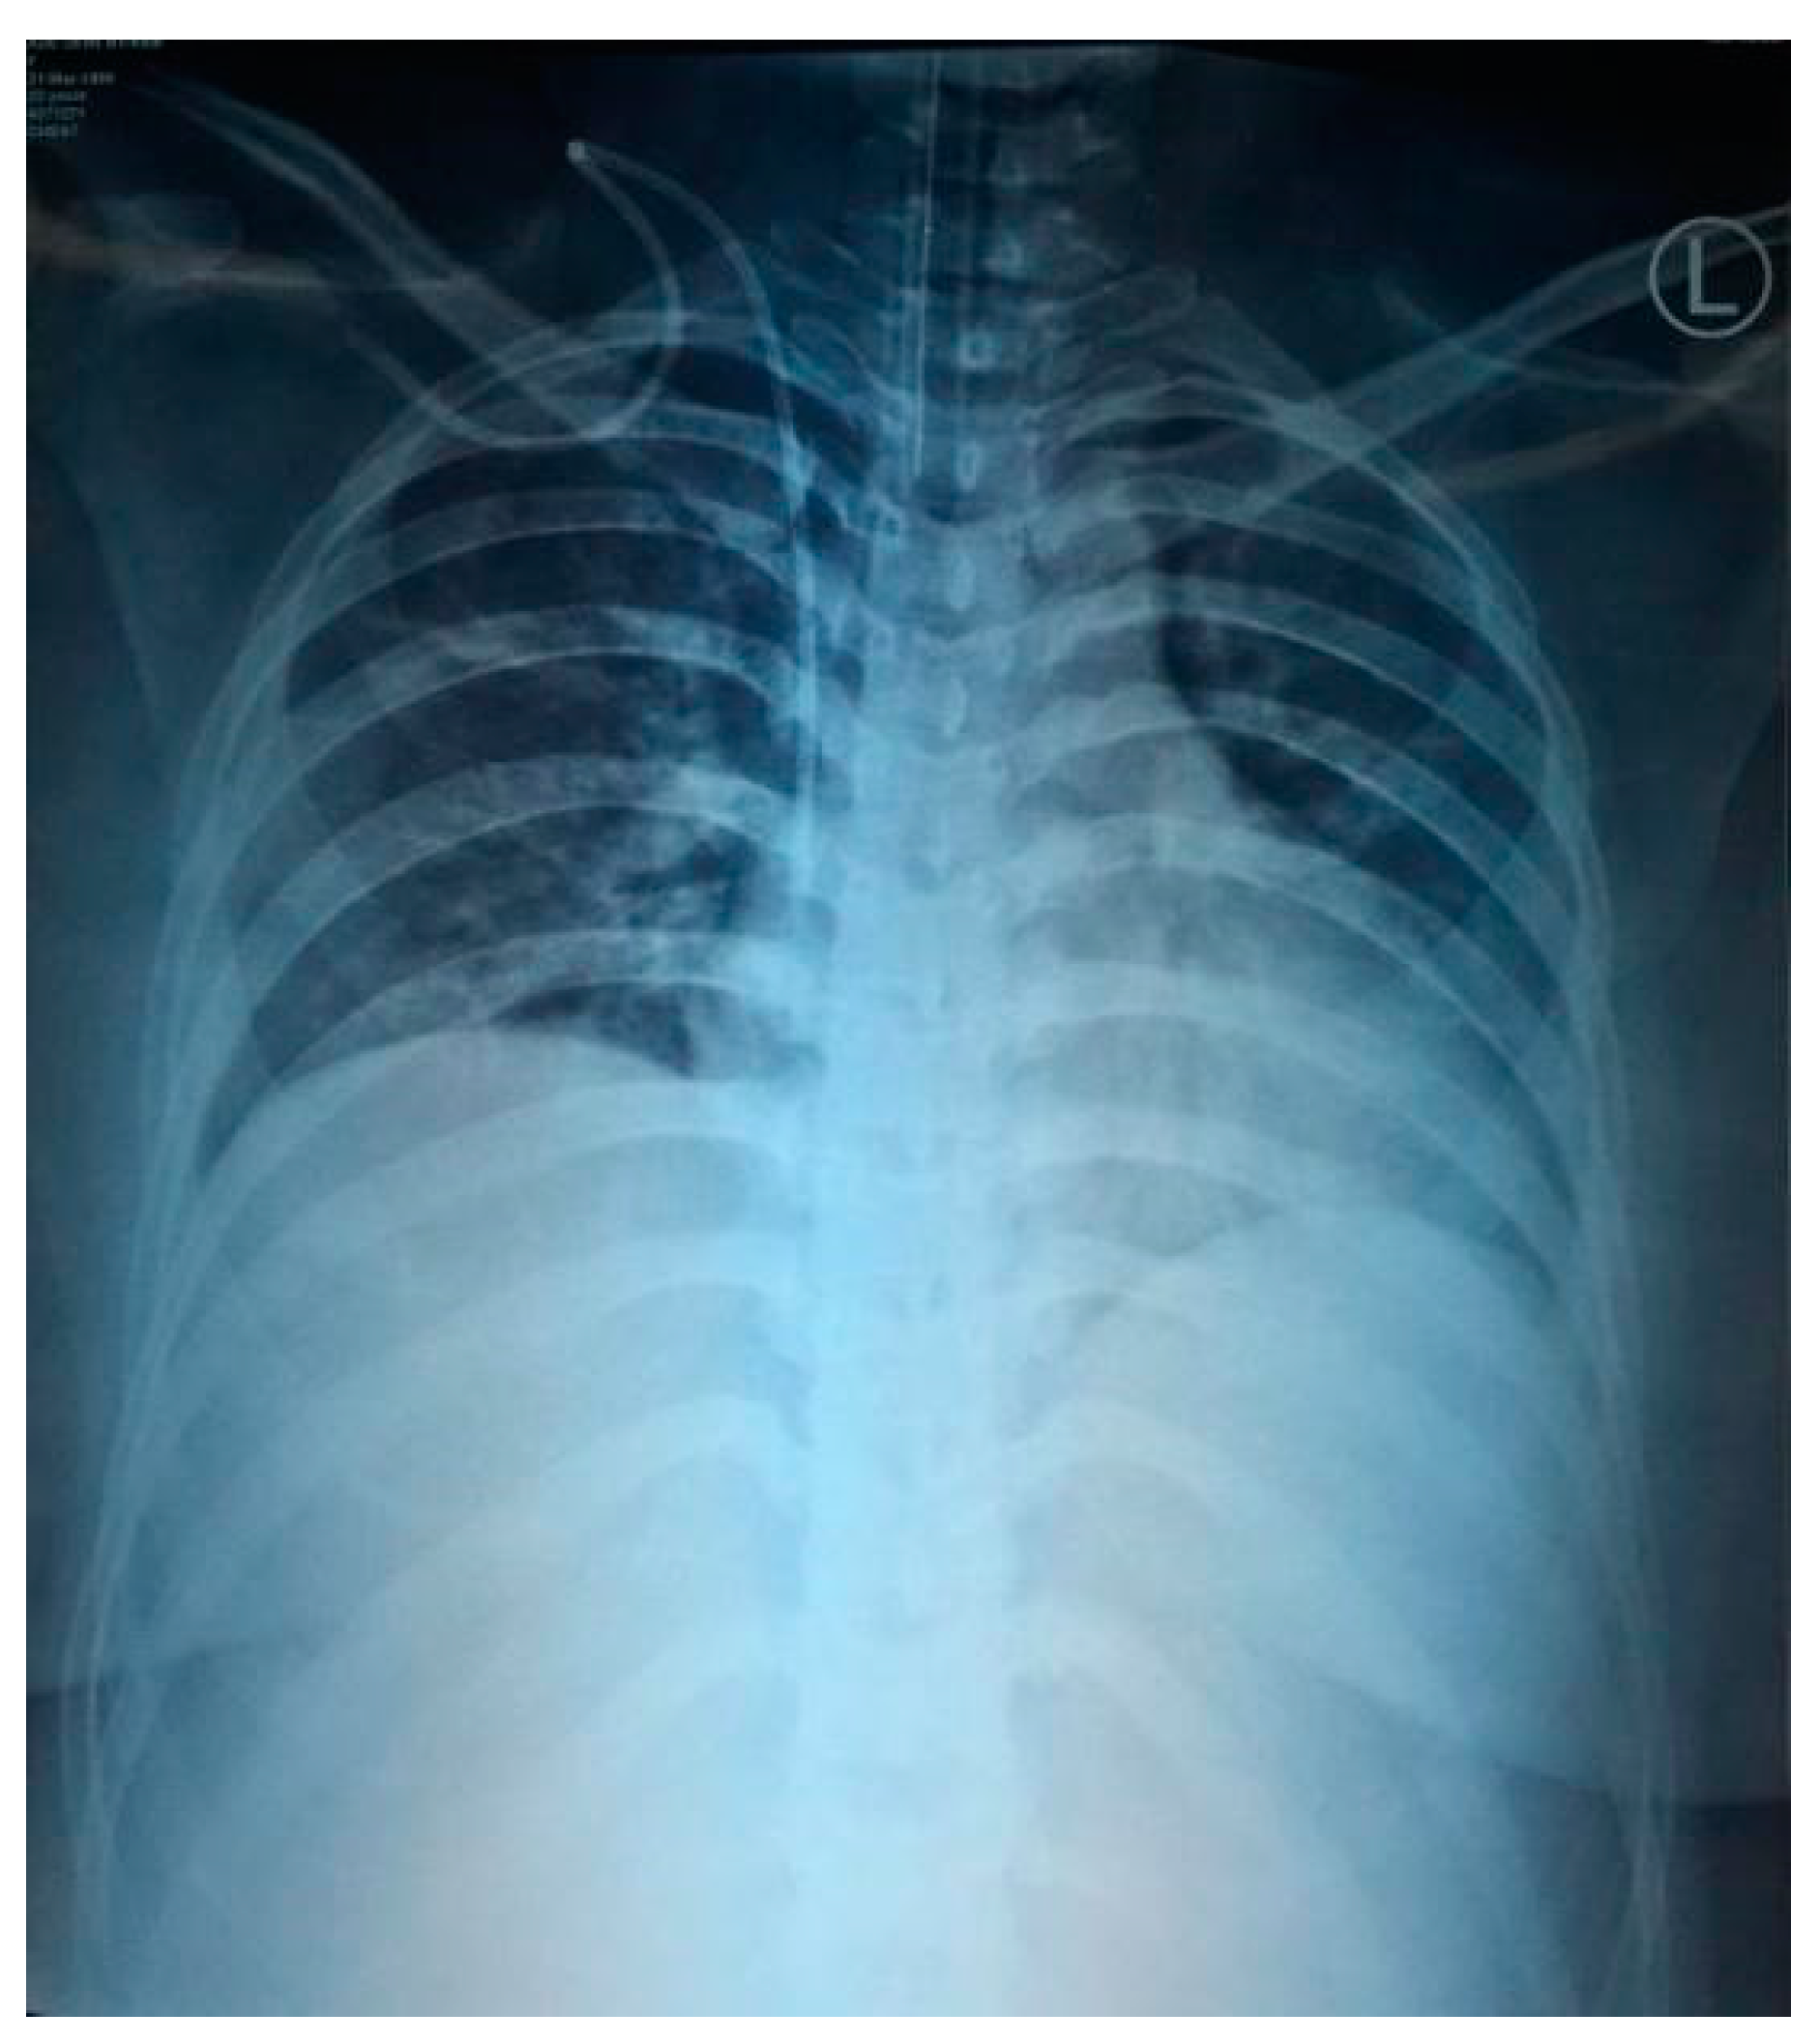

2.1. Case 1

2.2. Case 2

2.3. Case 3

2.4. Case 4